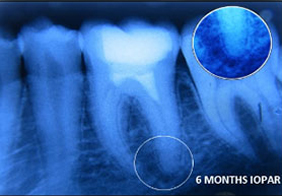

A case of combined REP in one Root and VPT in another Root.

Wound in bone (marked) in one root has healed through REP which is revealed in 6 and 12 months follow up IOPAR, the unaffected pulp in another Root Canal is protected through VPT resulting in the maintenance of validity of Tooth.